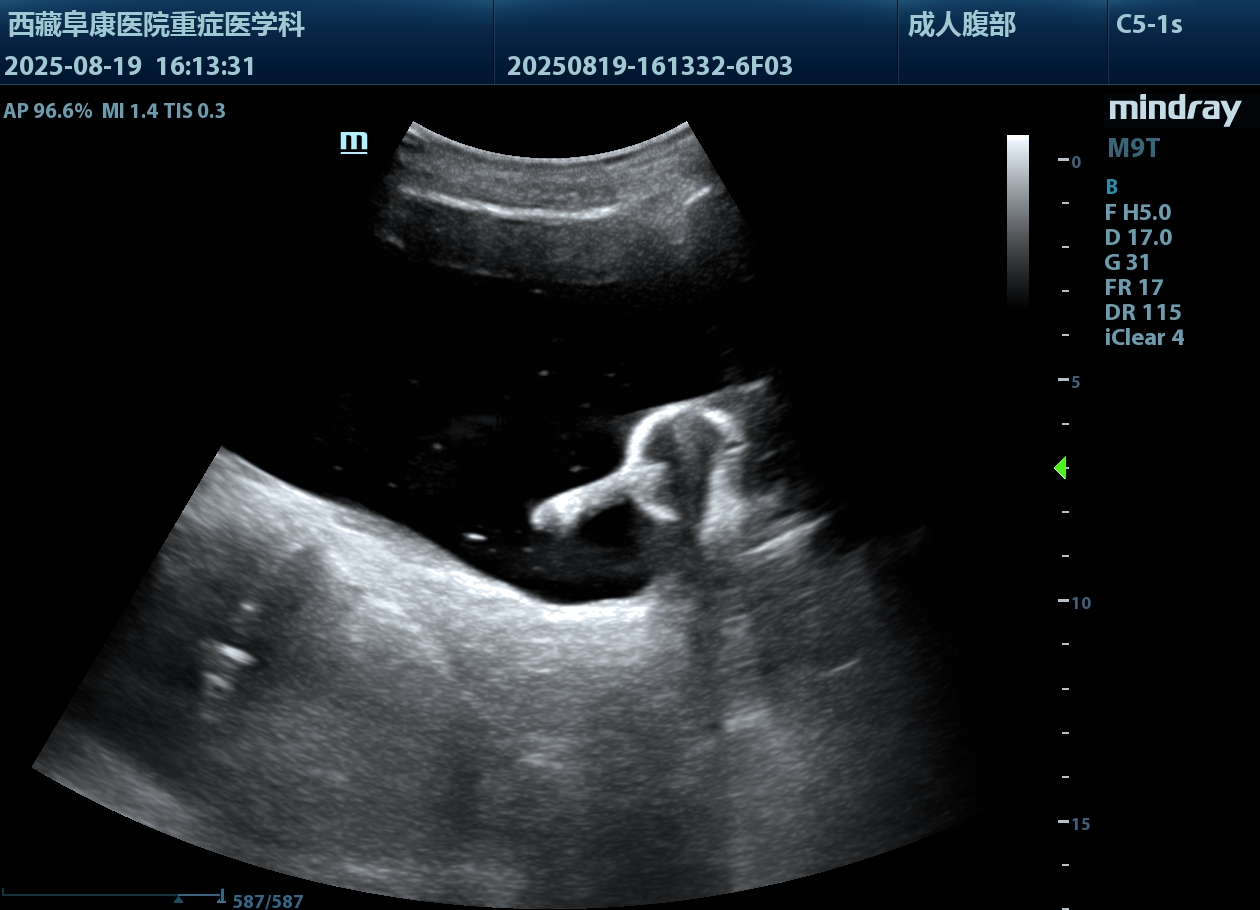

由于情況緊急,醫(yī)護(hù)人員沒(méi)有半分遲疑,除了導(dǎo)尿所需的物品,考慮到老人年紀(jì)大了,必須先確認(rèn)情況,半點(diǎn)馬虎不得,他們特意帶上B超機(jī),拎起出診箱,火速趕往老人家中。

推開(kāi)門,只見(jiàn)老人蜷縮在藏式床上,身子微微發(fā)顫。醫(yī)護(hù)人員放輕腳步,俯身輕聲安撫:“大爺,我們先幫您看看情況,不難受的?!毕仁禽p柔查體,感知膨隆小腹下的膀胱充盈度;再用B超機(jī)細(xì)致探查,醫(yī)護(hù)人員邊操作邊低聲講解流程。慢慢地老人緊繃的身體放松下來(lái),默許了檢查??墒翘岬綄?dǎo)尿時(shí),還是擺著手抗拒。醫(yī)護(hù)人員和家屬耐著性子反復(fù)勸說(shuō),許久后,他終于輕輕點(diǎn)了頭。